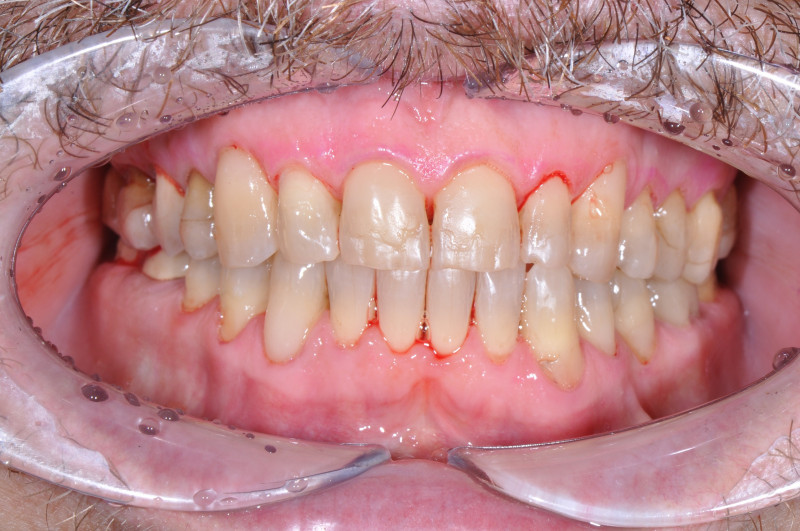

На странице представлено портфолио стоматологий Москвы с работами до и после профессиональной чистки зубов. В нашем портфолио собраны разные клинические случаи: от удаления незначительного налета до снятия массивного поддесневого камня. Здесь вы можете увидеть, как возвращается естественный цвет и внешний вид зубов после процедуры. Изучите результаты до и после чистки зубов, чтобы увидеть реальный эффект и выбрать клинику в Москве, где профессиональная гигиена поможет вернуть зубам здоровый вид.

Пациентке провели профгигиену зубов и полости рта и выровняли края зубов в зоне улыбки

Доктор: Карапетян Фреда Сергеевна